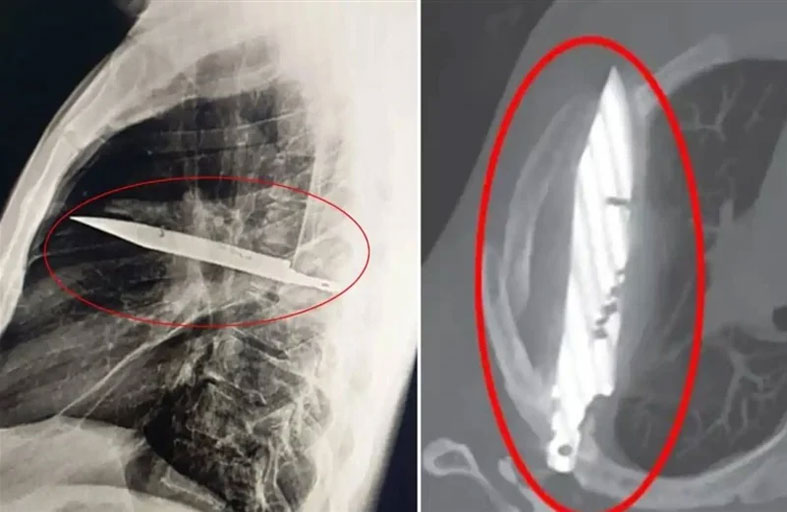

العثور على سكين مستقرة في صدر رجل 8 أعوام

في واقعة طبية نادرة، عثر أطباء في تنزانيا على سكين ضخم مغروس في صدر رجل مُنذ نحو 8 سنوات، بعد أن توجه إلى المستشفى شاكياً من آلام وإفرازات غريبة بمنطقة الصدر. وقالت التقارير الطبية إن الرجل، البالغ من العمر 44 عاماً، لم يكن يعاني من أي أعراض أخرى لافتة، إذ لم يشكُ من صعوبة في التنفس أو الحمى، كما كانت علاماته الحيوية طبيعية، وفقً لصحيفة "ذا صن" البريطانية. لكن فحوصات الأشعة كشفت عن وجود شيء معدني كبير اخترق جسده عبر لوح كتفه الأيمن، واستقر على مسافة خطيرة من أعضائه الحيوية، دون أن يلحظ طوال هذه السنوات. وبحسب المريض، فقد تعرض لإصابات متعددة في الوجه والظهر والصدر والبطن خلال "مشاجرة عنيفة" قبل نحو عقد، وتلقى حينها علاجاً، لكنه لم يكن يعلم أن السكين بقي عالقاً داخل جسده. وأجرى الجراحون عملية دقيقة لاستخراج السكين وتصريف الصديد الناتج عن تلف الأنسجة، فيما قضى المريض 24 ساعة في العناية المركزة، ثم 10 أيام في الجناح العام، قبل أن يتعافى ويغادر المستشفى بحالة مستقرة.